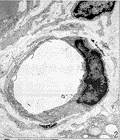

2.2 电镜观察 50 V神经损伤组:2 wk时,镜下观察无髓神经纤维有部分的空泡形成, 表现为轴突内微丝、微管等细胞器消失,呈低密度均质状态(Fig 1). 微血管内壁光滑,管腔无闭塞及栓塞(Fig 2),雪旺氏细胞轴突复合体无明显改变. 1 mo时,有髓神经、无髓神经结构已恢复正常,空泡现象消失,雪旺氏细胞形态正常. 3 mo时,神经结构未发现异常. 75 V神经损伤组:2 wk时,受损的神经纤维数目明显增加,损伤程度加重. 表现为无髓神经纤维轴膜破裂,轴浆外溢. 有髓神经纤维板层开始解体(Fig 3). 但微血管结构无明显变化. 仍可见到形态结构正常的神经纤维. 雪旺氏细胞形态无明显变化. 1 mo时,可见到新生的神经纤维,主要以两种形式存在. ①新生的神经纤维沿原有的溃变的神经膜管生长. 镜下可见到溃变解体的髓鞘内存有结构清晰的有髓神经纤维(Fig 4). ②新生的无髓神经纤维由雪旺氏细胞形成髓鞘逐渐包裹而成(Fig 5). 未得到神经再支配的神经纤维结构开始解体(Fig 6),无髓神经纤维轴膜破裂相互融合. 有髓神经纤维髓鞘厚薄不均,并溶解形成滴状结构. 3 mo时,再生的神经纤维结构进一步成熟. 可见新生髓鞘较薄,但外层光滑,亦可见到尚未完全形成包裹的板层髓鞘(Fig 7). 无髓神经纤维数目减少,但直径增大,雪旺氏细胞包裹的无髓神经纤维数目减少,并处于细胞的外层. 胶原纤维无明显增加. 200 V神经损伤组:1 wk时,镜下观血管内膜凹凸不平,管腔内有血栓形成(Fig 8). 无髓神经纤维变性,雪旺氏细胞数量减少. 有髓神经髓板全部呈松散结构,板层分离. 1 mo时,镜下观血管内膜凹凸不平加重,管腔完全闭塞. 胶原纤维含量开始增加. 雪旺氏细胞基膜与轴突分离,髓鞘厚薄不均,髓鞘板层松散呈丝瓜囊状(Fig 9). 3 mo时,镜下见胶原纤维含量明显增加,占据大部分视野. 无髓神经纤维消失,有髓神经纤维板层分离并皱缩成团,轴突管腔消失成为实心结构. 雪旺氏细胞结构消失.

图 1 无髓神经纤维有部分的空泡形成

图 2 微血管内壁光滑,管腔无闭塞及栓塞